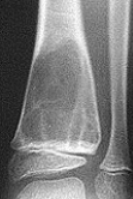

| What disease is this? | Osteoarthritis |